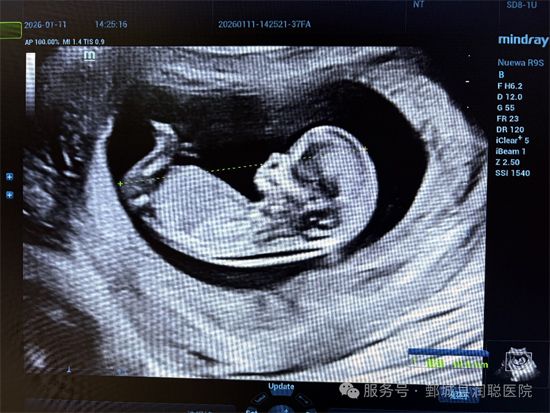

NT的全称是“胎儿颈后透明层”(nuchal translucency),指的是孕11~13⁺⁶周时,胎儿颈后皮下的一层无回声透明带。这层透明带的厚度,是早期筛查胎儿染色体异常(如唐氏综合征)和心脏等结构畸形的重要指标。

医生需要找到胎儿的正中矢状切面(类似“侧脸照”),清晰显示鼻骨、皮肤线和颈部透明层,同时放大图像,让胎儿占满屏幕的70%以上。

测量游标必须垂直于胎儿皮肤,放在透明层的zui宽处,轻微移动游标只能改变0.1mm的 读数,多次测量后取zui大值。